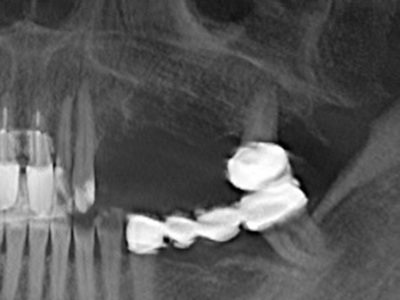

Fig. 27: 21-year-old patient after conversion osteotomy with persistent retrognathy with class II dysgnathy.

Fig. 28: During removal of metal, the basal chin regions are separated with the Piezomed while retaining the lingual blood supply.

Fig. 29: Forward displacement of the chin by 5 mm and fixation with two osteosynthesis plates (KLS Martin). The two mental nerves can be detected in the marginal region.

Fig. 30: The aesthetic improvement in the chin contour after the operation can be clearly seen.